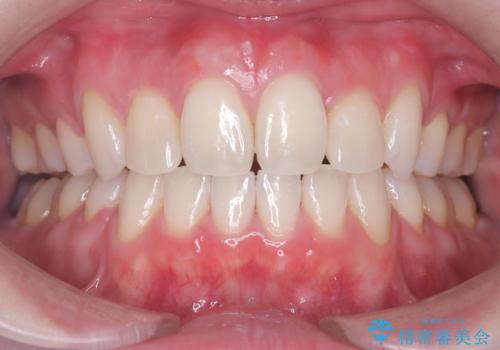

上下4本の抜歯と審美ワイヤー矯正で整った歯並びへ

- 患者様は、歯並びの乱れを整えたいとのことで来院されました。診察の結果、歯列のスペース不足が原因で前歯のガタつきが目立ち、噛み合わせにも影響が出ている状態でした。歯を正しく並べるためにはスペースの確保が必要と判断し、上下の小臼歯4本を抜歯して、審美ワイヤー矯正(白いワイヤーと透明ブラケット)で治療を行う計画を立てました。

まず、抜歯によって歯を動かすためのスペースを確保。その後、審美ワイヤー矯正を用いて、前歯のガタつきを整えながら、噛み合わせの調整も行いました。審美装置を使用することで、矯正中も目立ちにくく、自然な仕上がりを目指して治療を進めました。治療の結果、歯並びがきれいに整い、口元のバランスも改善しました。患者様からは「歯並びがきれいになり、自信を持って笑えるようになった」と喜びの声をいただきました。